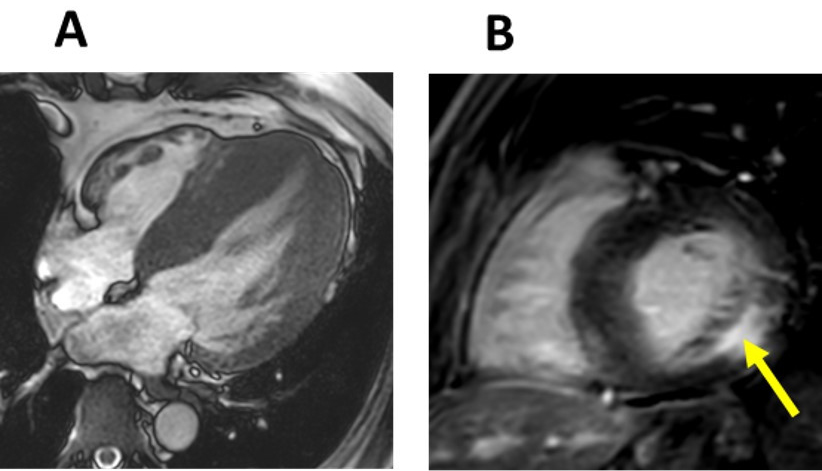

LVH in FD typically presents a concentric pattern (Fig. 2) without resting left ventricular outflow tract obstruction (LVOTO). However, obstructive forms, asymmetric septal (Fig. 3), apical and eccentric hypertrophy have also been described [19, 20]. In fact, LVOTO may be more prevalent and have a greater impact on symptoms than was previously thought. In a small cohort of 14 patients, LVOTO was revealed by exercise stress echocardiography in six patients with refractory symptoms [21]. A smaller cavity size and papillary muscle (PM) hypertrophy were speculated to be involved in the LVOTO.

Fig. 2.Left ventricular and papillary muscle hypertrophy in Fabry disease. Echocardiography four-chamber view (A) and short-axis CMR image (B) that shows a severe left ventricular hypertrophy and papillary muscle hypertrophy (arrows) in a 47-year-old male patient with Fabry disease.

Disproportionate hypertrophy of PM could also be a useful marker of FD (Fig. 2).